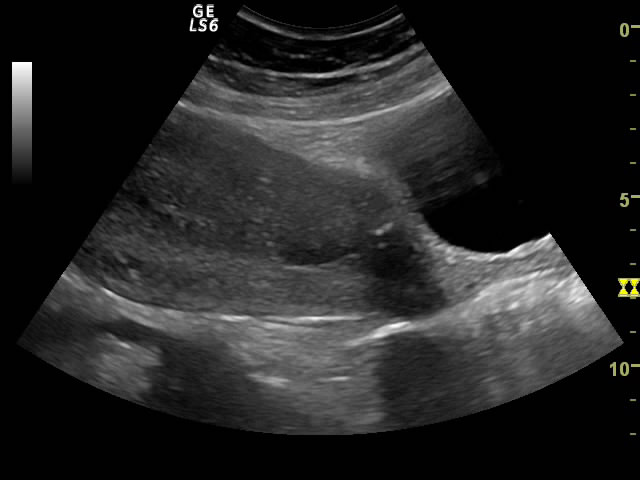

ASPECTE ECOGRAFICE IN LAUZIE

ASPECTE ECOGRAFICE IN LAUZIE             Involutia uterina poate fi urmarita si ecografic.             Complicatiile lauziei ca febra si sangerarile pot avea imagini ecografice specifice. Datorita marimii uterului in lauzie, ecografia a